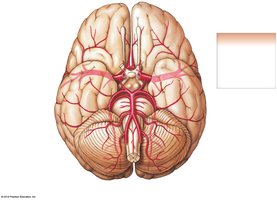

Circulation to the Brain

Blood supply to the brain is provided by the internal and external carotid arteries and vertebral arteries. The Cerebral Arterial Circle (Circle of Willis) ensures continuous blood flow to the brain.

Internal carotid → middle and anterior cerebral arteries

Vertebral arteries → basilar artery → posterior cerebral arteries